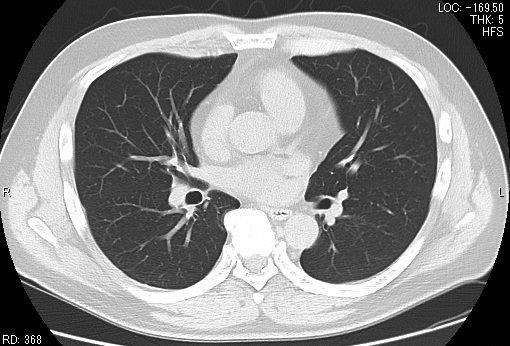

CT

CTとはコンピュータ断層撮影(computed tomography)の略です。

CT検査は、ベッドをスライドさせながらX線撮影をし、それをコンピュータ処理して画像にする検査です。

当院では64列CTを導入し、従来のCT装置では難しかった心臓の検査をはじめ、データを3次元的に収集するため、あらゆる方向の画像を再構成でき、3D画像も作成できます。

64列になったことにより、速やかに、低被ばくで検査ができ、鮮明な画像を得ることができます。

胸部